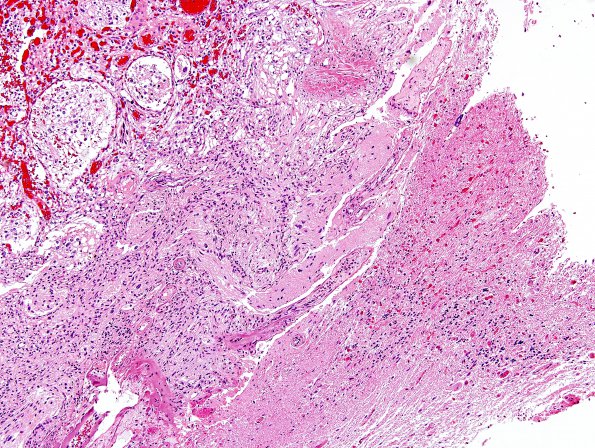

Washington University Experience | NEOPLASMS (MESENCHYMAL, NON-MENINGOTHELIAL) | Hemangioblastoma | 3B2 Hemangioblastoma (Case 3) H&E 2B

The margin of the tumor (arrowhead, 3B1) with surrounding brain tissue shows prominent gliosis and numerous Rosenthal fibers.